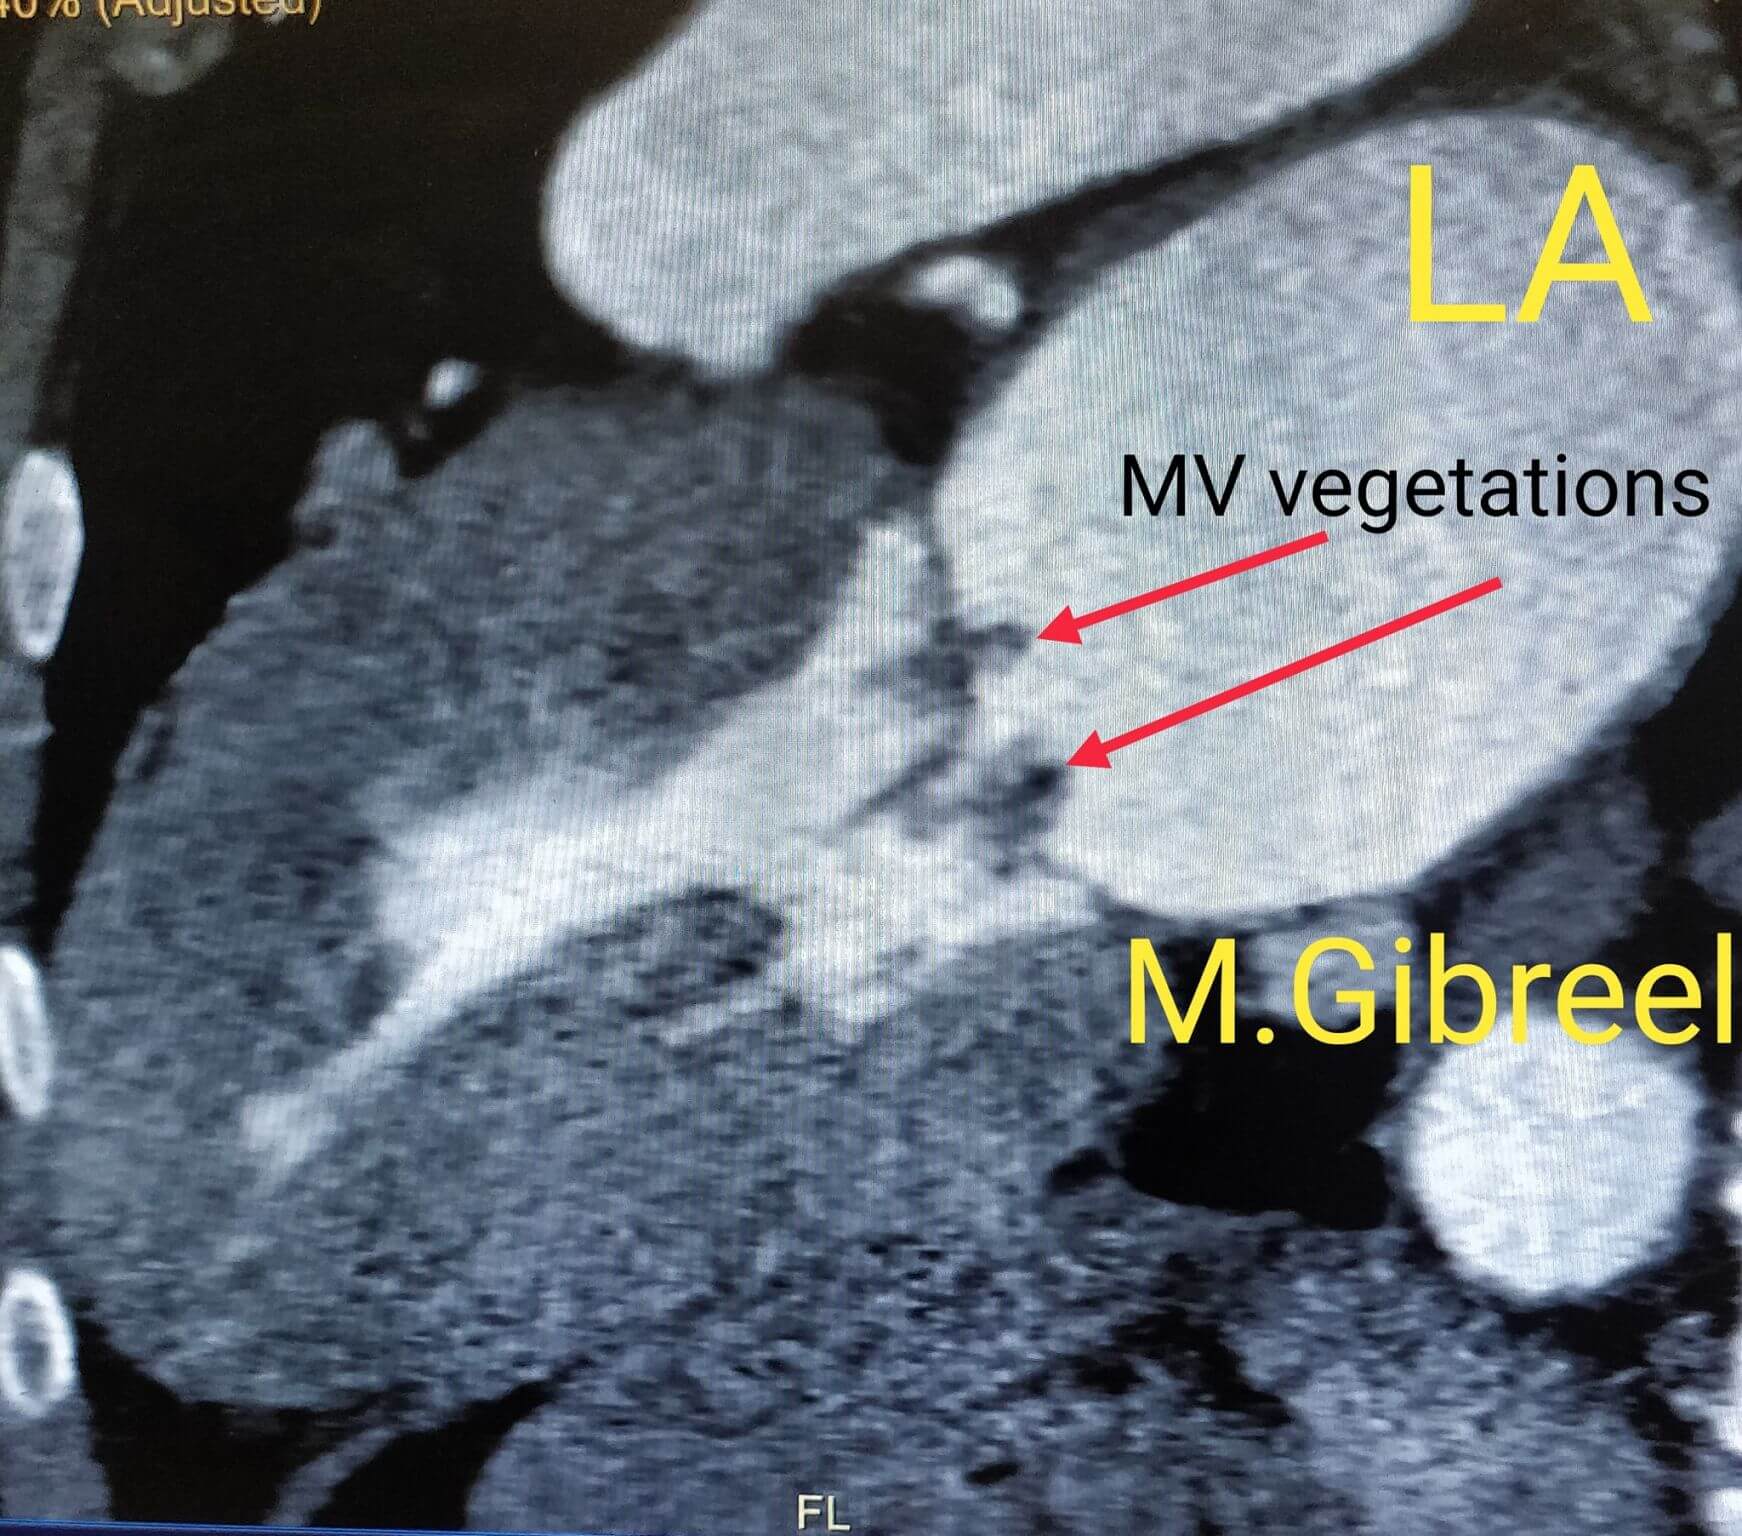

Mohamed Gibreel , FEBR (Fellowship of Egyptian Board of Radiology ) Cardiac imaging consultant at Aswan heart center -Magdi Yacoub Foundation , Egypt